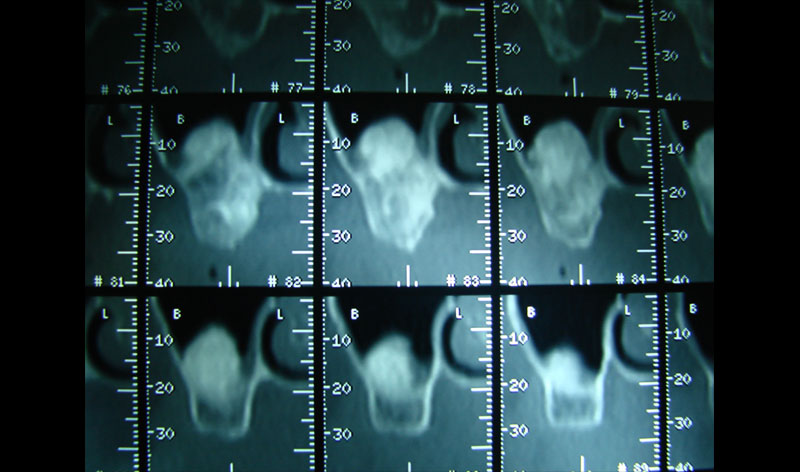

Existen muchas situaciones donde la pérdida y la atrofia ósea son tan graves que nos obligan a recurrir a la cresta iliaca del paciente, para conseguir el volumen óseo necesario para la correcta reconstrucción del maxilar. Así, la colocación de implantes será posible a los 3 meses.